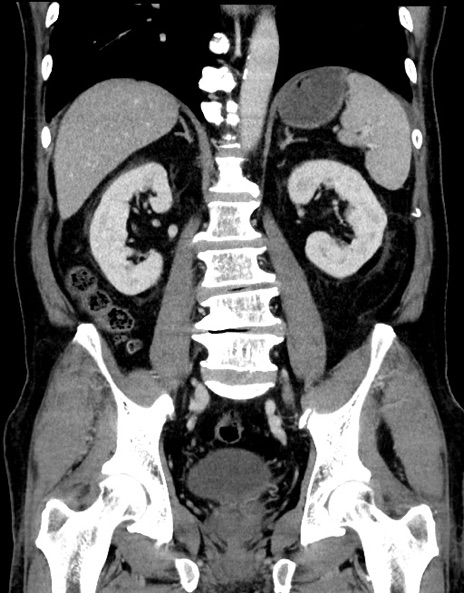

症例15(冠状断像)

【症例】70歳代男性

【主訴】腹痛

【現病歴】今朝から腹痛あり。全体的に痛い。特に左上の方。排ガスが今日はない。冷や汗が出る。

【既往歴】直腸癌術後

【身体所見】左側腹部〜上腹部に圧痛あり。腹膜刺激症状明らかなではない。軽度反跳痛。左下腹部に術後瘢痕あり。

【データ】WBC 7700、CRP 0.02